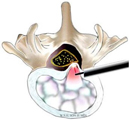

上図は椎間孔アプローチです(左図)。内視鏡を椎間板に平行にして椎間板ヘルニアに近づけます(中央図)。椎間板ヘルニアを摘出しています(右図)。

経椎弓アプローチで椎間板ヘルニアを摘出(左)、MELと同様に片側進入両側除圧が可能で、PEL法ともいわれています。PEL法は術後硬膜外血腫のリスクが高いので、血液を創から排出するためのドレーンを長く(4日程度)留置します。